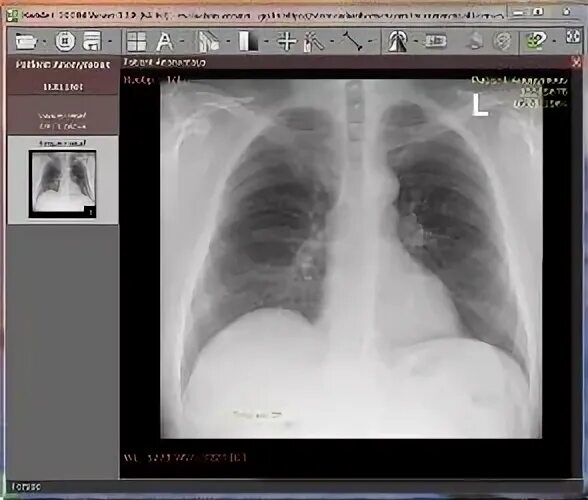

Радиант программа для кт